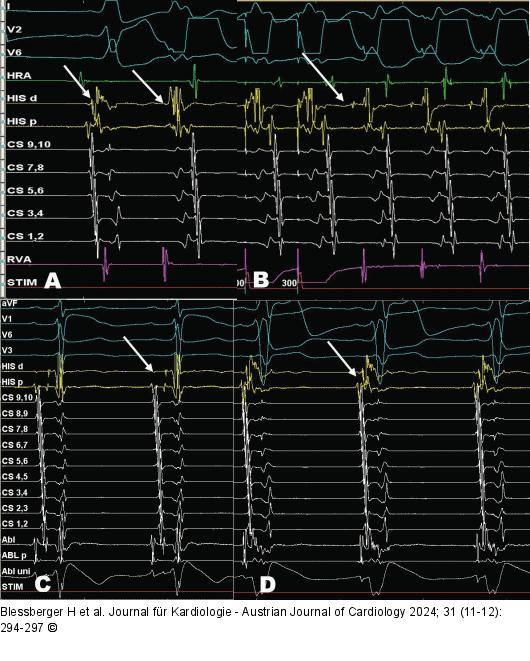

Abbildung 2: HRA-Katheter - His-Katheter - CS-Katheter - RVA-Katheter Elektrophysiologische Untersuchung mit HRA-, His-, CS- und RVA-Kathetern. (A): Im Sinusrhythmus zeigt sich ein deutliches Fusionspotenzial (Pfeil) im Bereich des distalen His. Auch bei einer spontanen ventrikulären Extrasystole ist die früheste atriale Erregung im Fusionspotenzial an der distalen His-Elektrode. (B): Unter programmierter ventrikulärer Stimulation mit 300 ms kann eine orthodrome AV-Reentrytachykardie mit einer Zykluslänge von 330 ms ausgelöst werden (Pfeil). Früheste retrograde atriale Signale befinden sich am distalen His-Kanal. (C): Nach mechanischer Irritation der His-Region durch den Ablationskatheter ist die Bahn refraktär und ein klassisches His-Signal (Pfeil) kann abgeleitet werden. (D): Schon nach wenigen Minuten erholt sich aber die Bahnleitung erneut (Pfeil). Das His-Signal ist nun wieder im Ventrikelsignal verborgen. |

Elektrophysiologische Untersuchung mit HRA-, His-, CS- und RVA-Kathetern. (A): Im Sinusrhythmus zeigt sich ein deutliches Fusionspotenzial (Pfeil) im Bereich des distalen His. Auch bei einer spontanen ventrikulären Extrasystole ist die früheste atriale Erregung im Fusionspotenzial an der distalen His-Elektrode. (B): Unter programmierter ventrikulärer Stimulation mit 300 ms kann eine orthodrome AV-Reentrytachykardie mit einer Zykluslänge von 330 ms ausgelöst werden (Pfeil). Früheste retrograde atriale Signale befinden sich am distalen His-Kanal. (C): Nach mechanischer Irritation der His-Region durch den Ablationskatheter ist die Bahn refraktär und ein klassisches His-Signal (Pfeil) kann abgeleitet werden. (D): Schon nach wenigen Minuten erholt sich aber die Bahnleitung erneut (Pfeil). Das His-Signal ist nun wieder im Ventrikelsignal verborgen. |